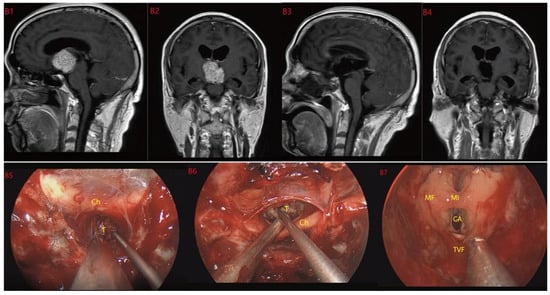

Figure 5.

Case 5 Type III: the tumor grows strictly inside the third ventricle. (B1,B2) The TCPCA AND TLTA was used; the pituitary stalk could not be seen during the surgery (B5–B7). The TVF was intact. The tumor was finally totally resection (B3,B4). Optic chiasm (Ch), foramen of Monroe (MF), massa intermedia (MI), cerebral aqueduct (CA), tumor (T).